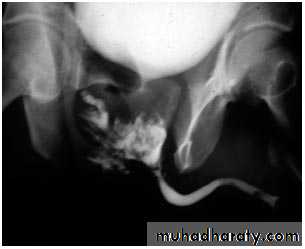

male &female reproductive tractsmammogram

genital tract and mammogram